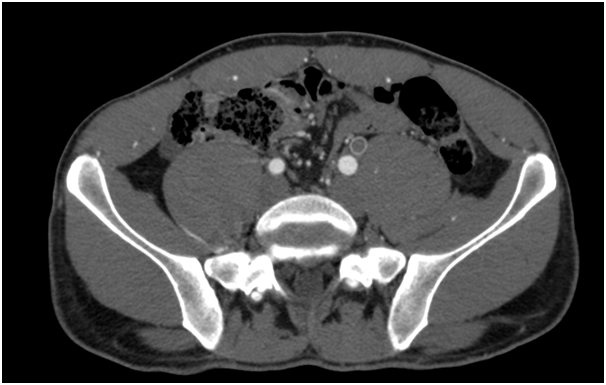

One year later he was visited for the appearance of ischemic symptoms in the right lower limb, calf claudication, pulselessness and subtle pallor, with no critical ischemia signs. An emergency duplex ultrasound evaluation showed a pathological Doppler curve and lowered systolic blood flow speed in the right femoral artery thus suggesting iliac stenosis. With the diagnostic orientation of a complicated right EIA endofibrosis, low molecular weight heparin was prescribed to avoid progressive thrombosis and a new angio CT scan was performed. The CT scan demonstrated an acute thrombosis of the right EIA, with patency of the previously revascularized left EIA, and an endovascular revascularization was programmed (Figure 1) (Figure 2).

Figure 2 CT scan oblique reconstruction showing occlusion of the right EIA, the occluded iliac prosthetic graft and patency of the native left iliac arteries after revascularization.